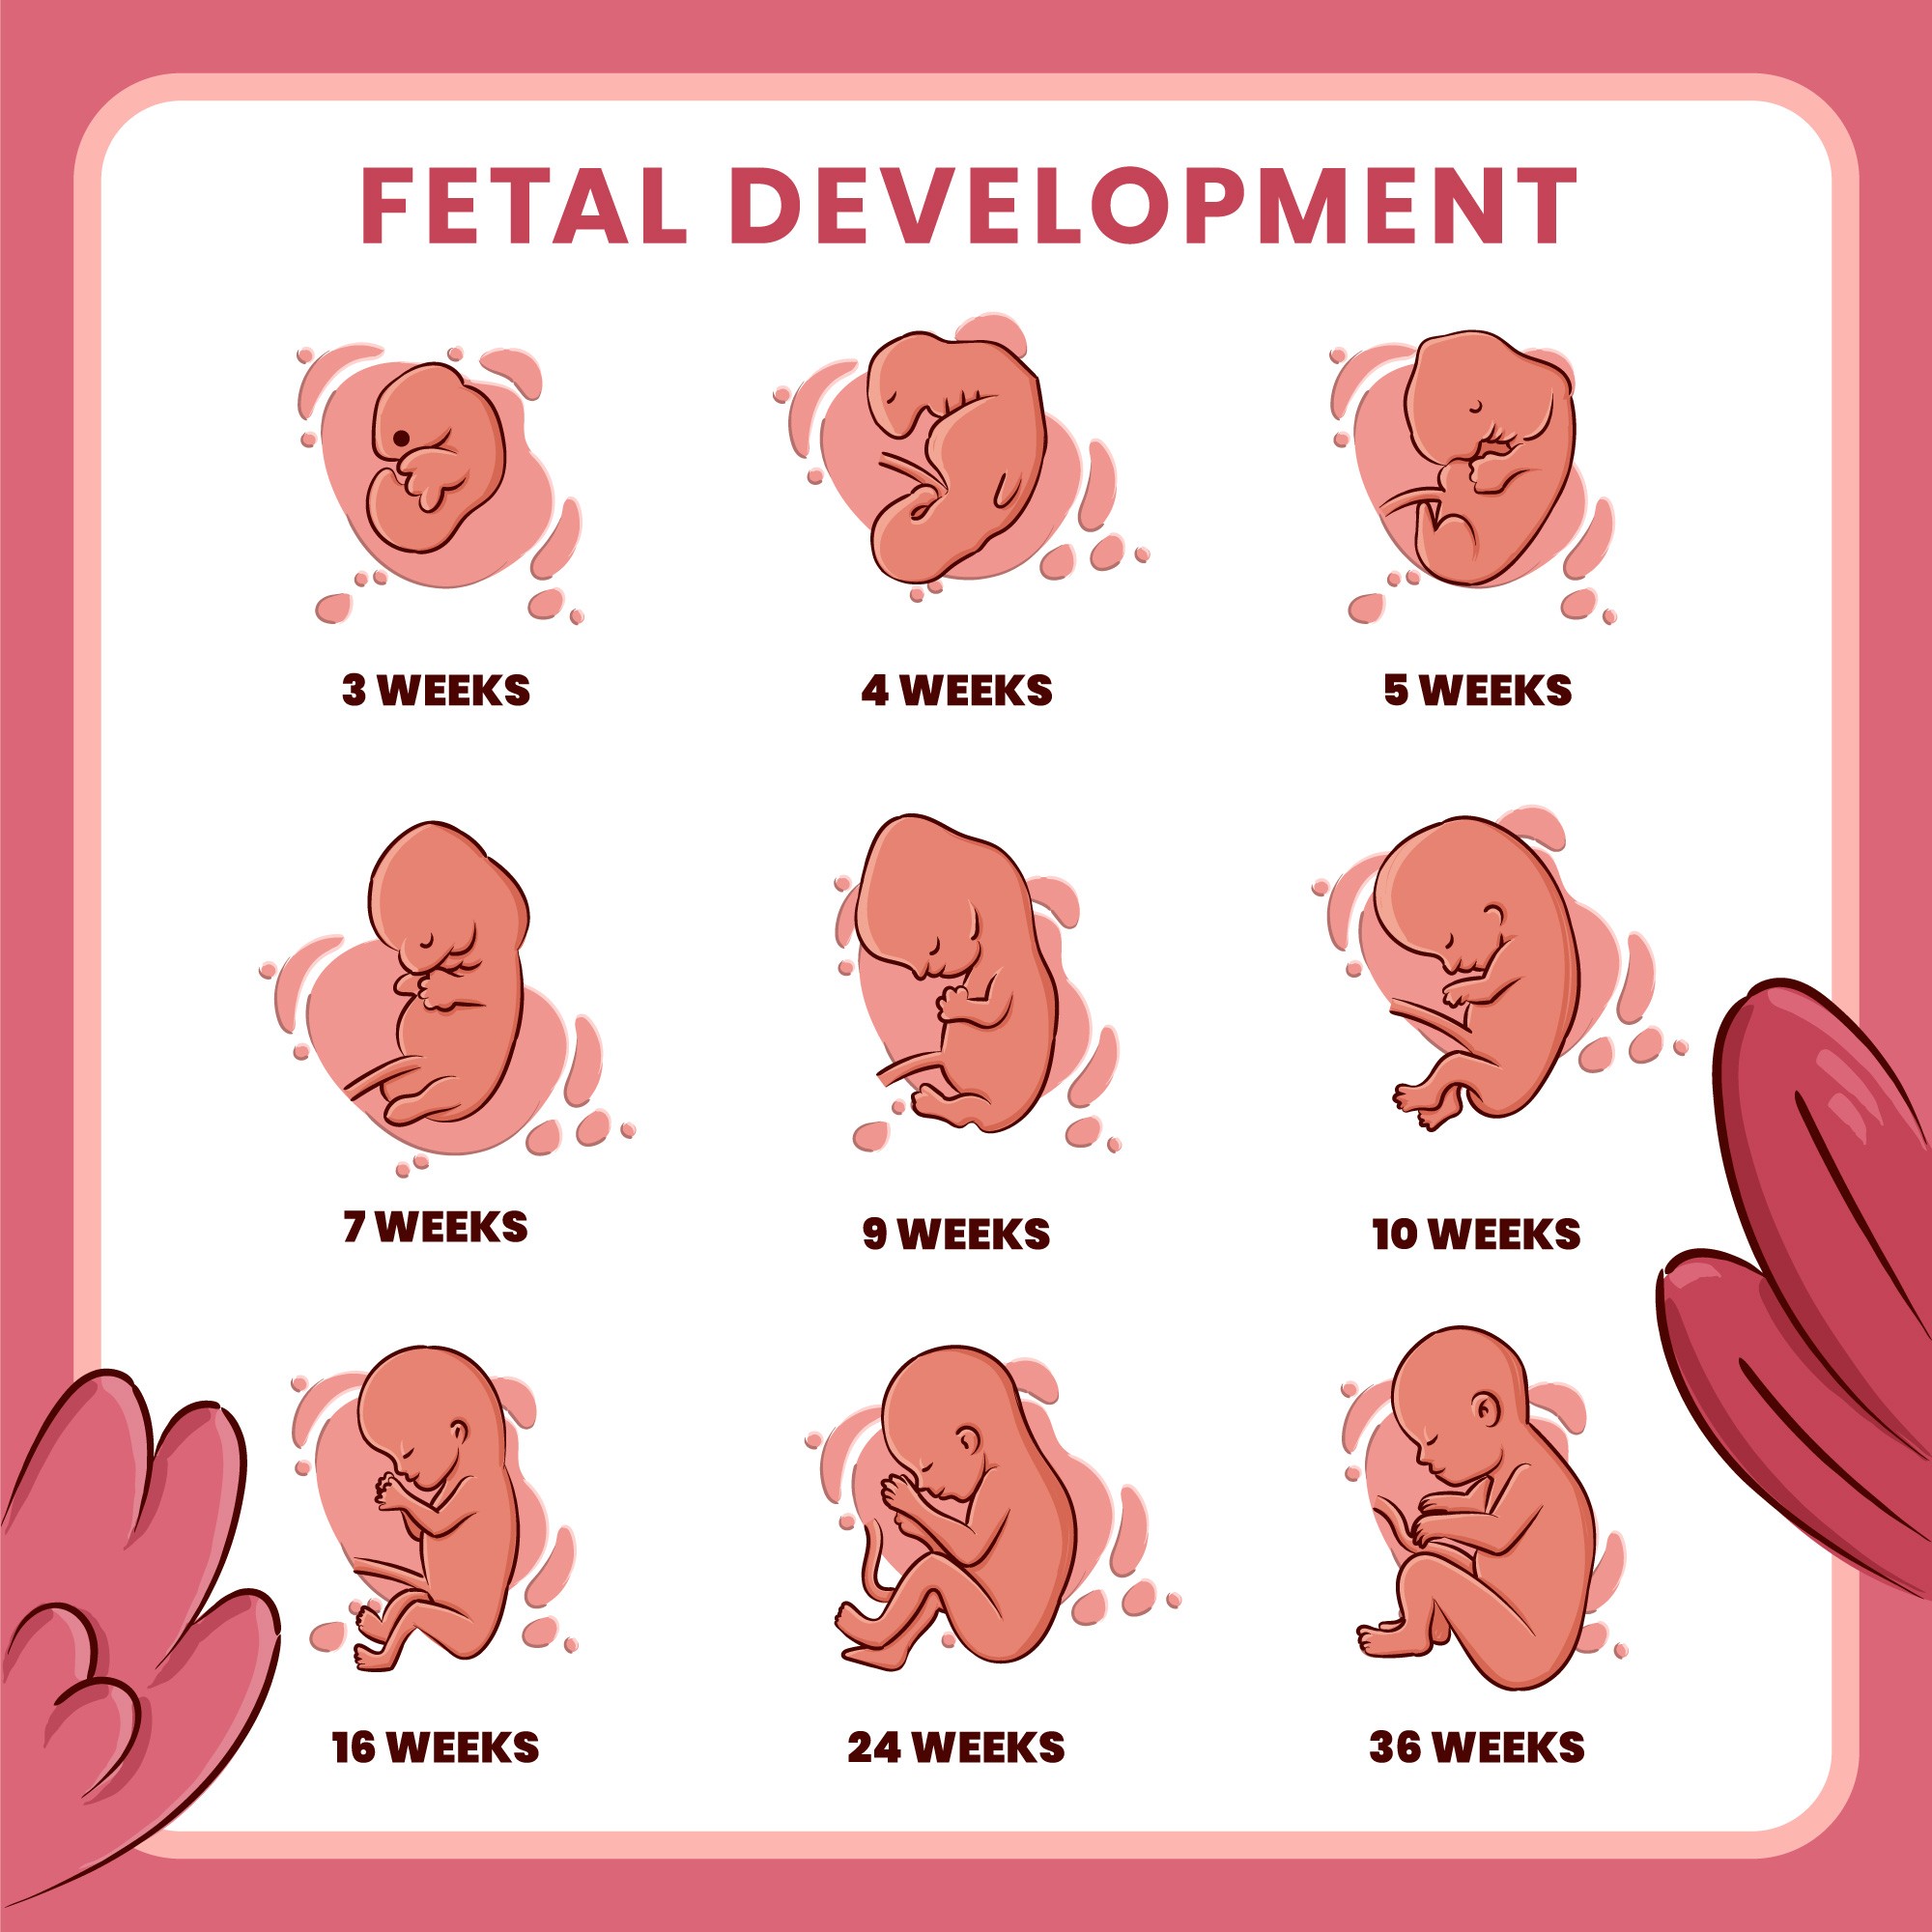

Kematian Janin di Dalam Rahim (IUFD)

Kematian janin intra-uterine adalah kondisi medis untuk kematian janin yang terjadi pada atau setelah usia kehamilan 20 minggu atau trimester kedua.

Pertumbuhan Janin Terhambat (IUGR)

Pertumbuhan janin terhambat (IUGR) adalah kondisi dimana janin lebih kecil daripada ukuran normal untuk usia kehamilannya